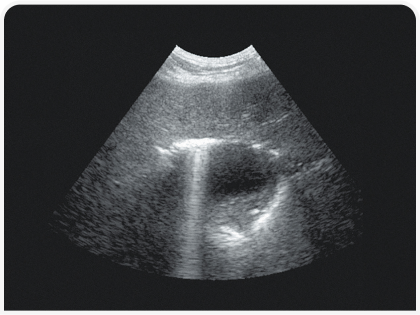

Рентгенография позволяет определить размеры, форму, положение, непрозрачность и края печени, а также обнаружить скопления газа или минерализацию (Рисунок 2). Ультразвуковое исследование помогает определить распространенность поражения печени (очаговое, многоочаговое или диффузное), а также оценить степень васкуляризации и облегчить получение образцов (для цитологического и культурального исследований и биопсии) (Рисунок 3). Однако следует помнить, что отсутствие патологических изменений при ультразвуковом исследовании не всегда свидетельствует о здоровье печени.